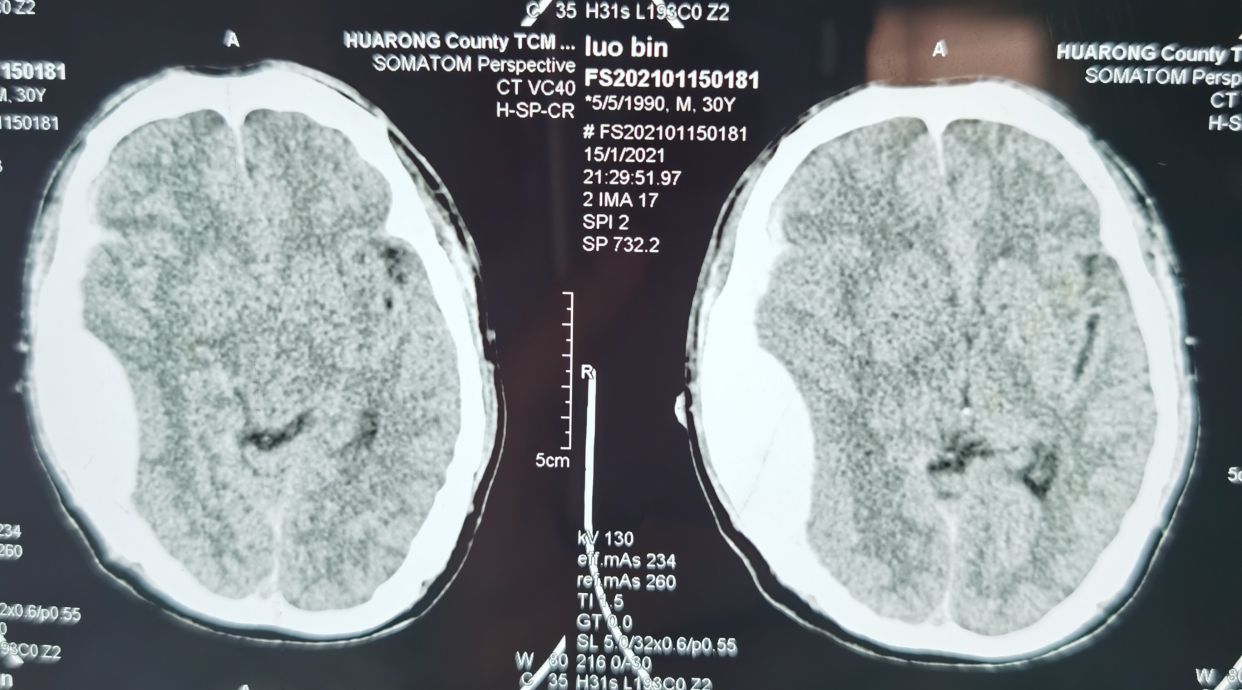

入院时完善头部CT如下:提示硬膜外血肿并脑疝,硬膜下少量出血。

然而,这个真的就一定是硬膜外血肿吗?